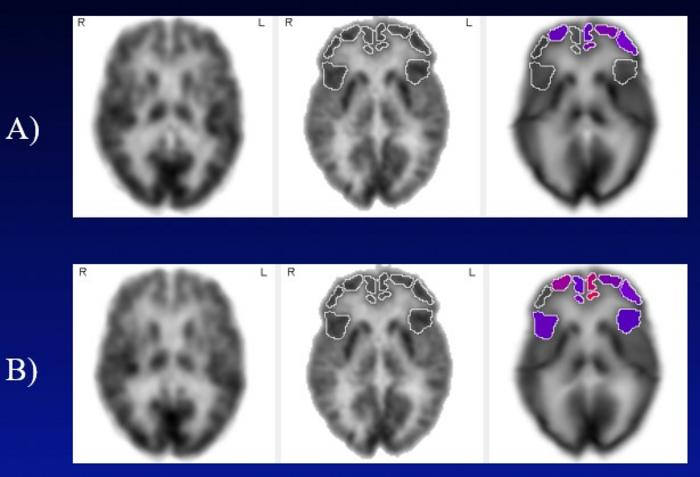

Row A: Frontal cortical regions with below-normal metabolism (less than 5th percentile, displayed in color) at baseline, in subjects with mild cognitive impairment and untreated hearing loss.

Row B: Frontal cortical regions with below-normal metabolism two years later. Brighter red colors correspond to a more severely diminished metabolism. In contrast, the group of subjects using hearing aids did not undergo a significant decline in any frontal cortical region over the same time.